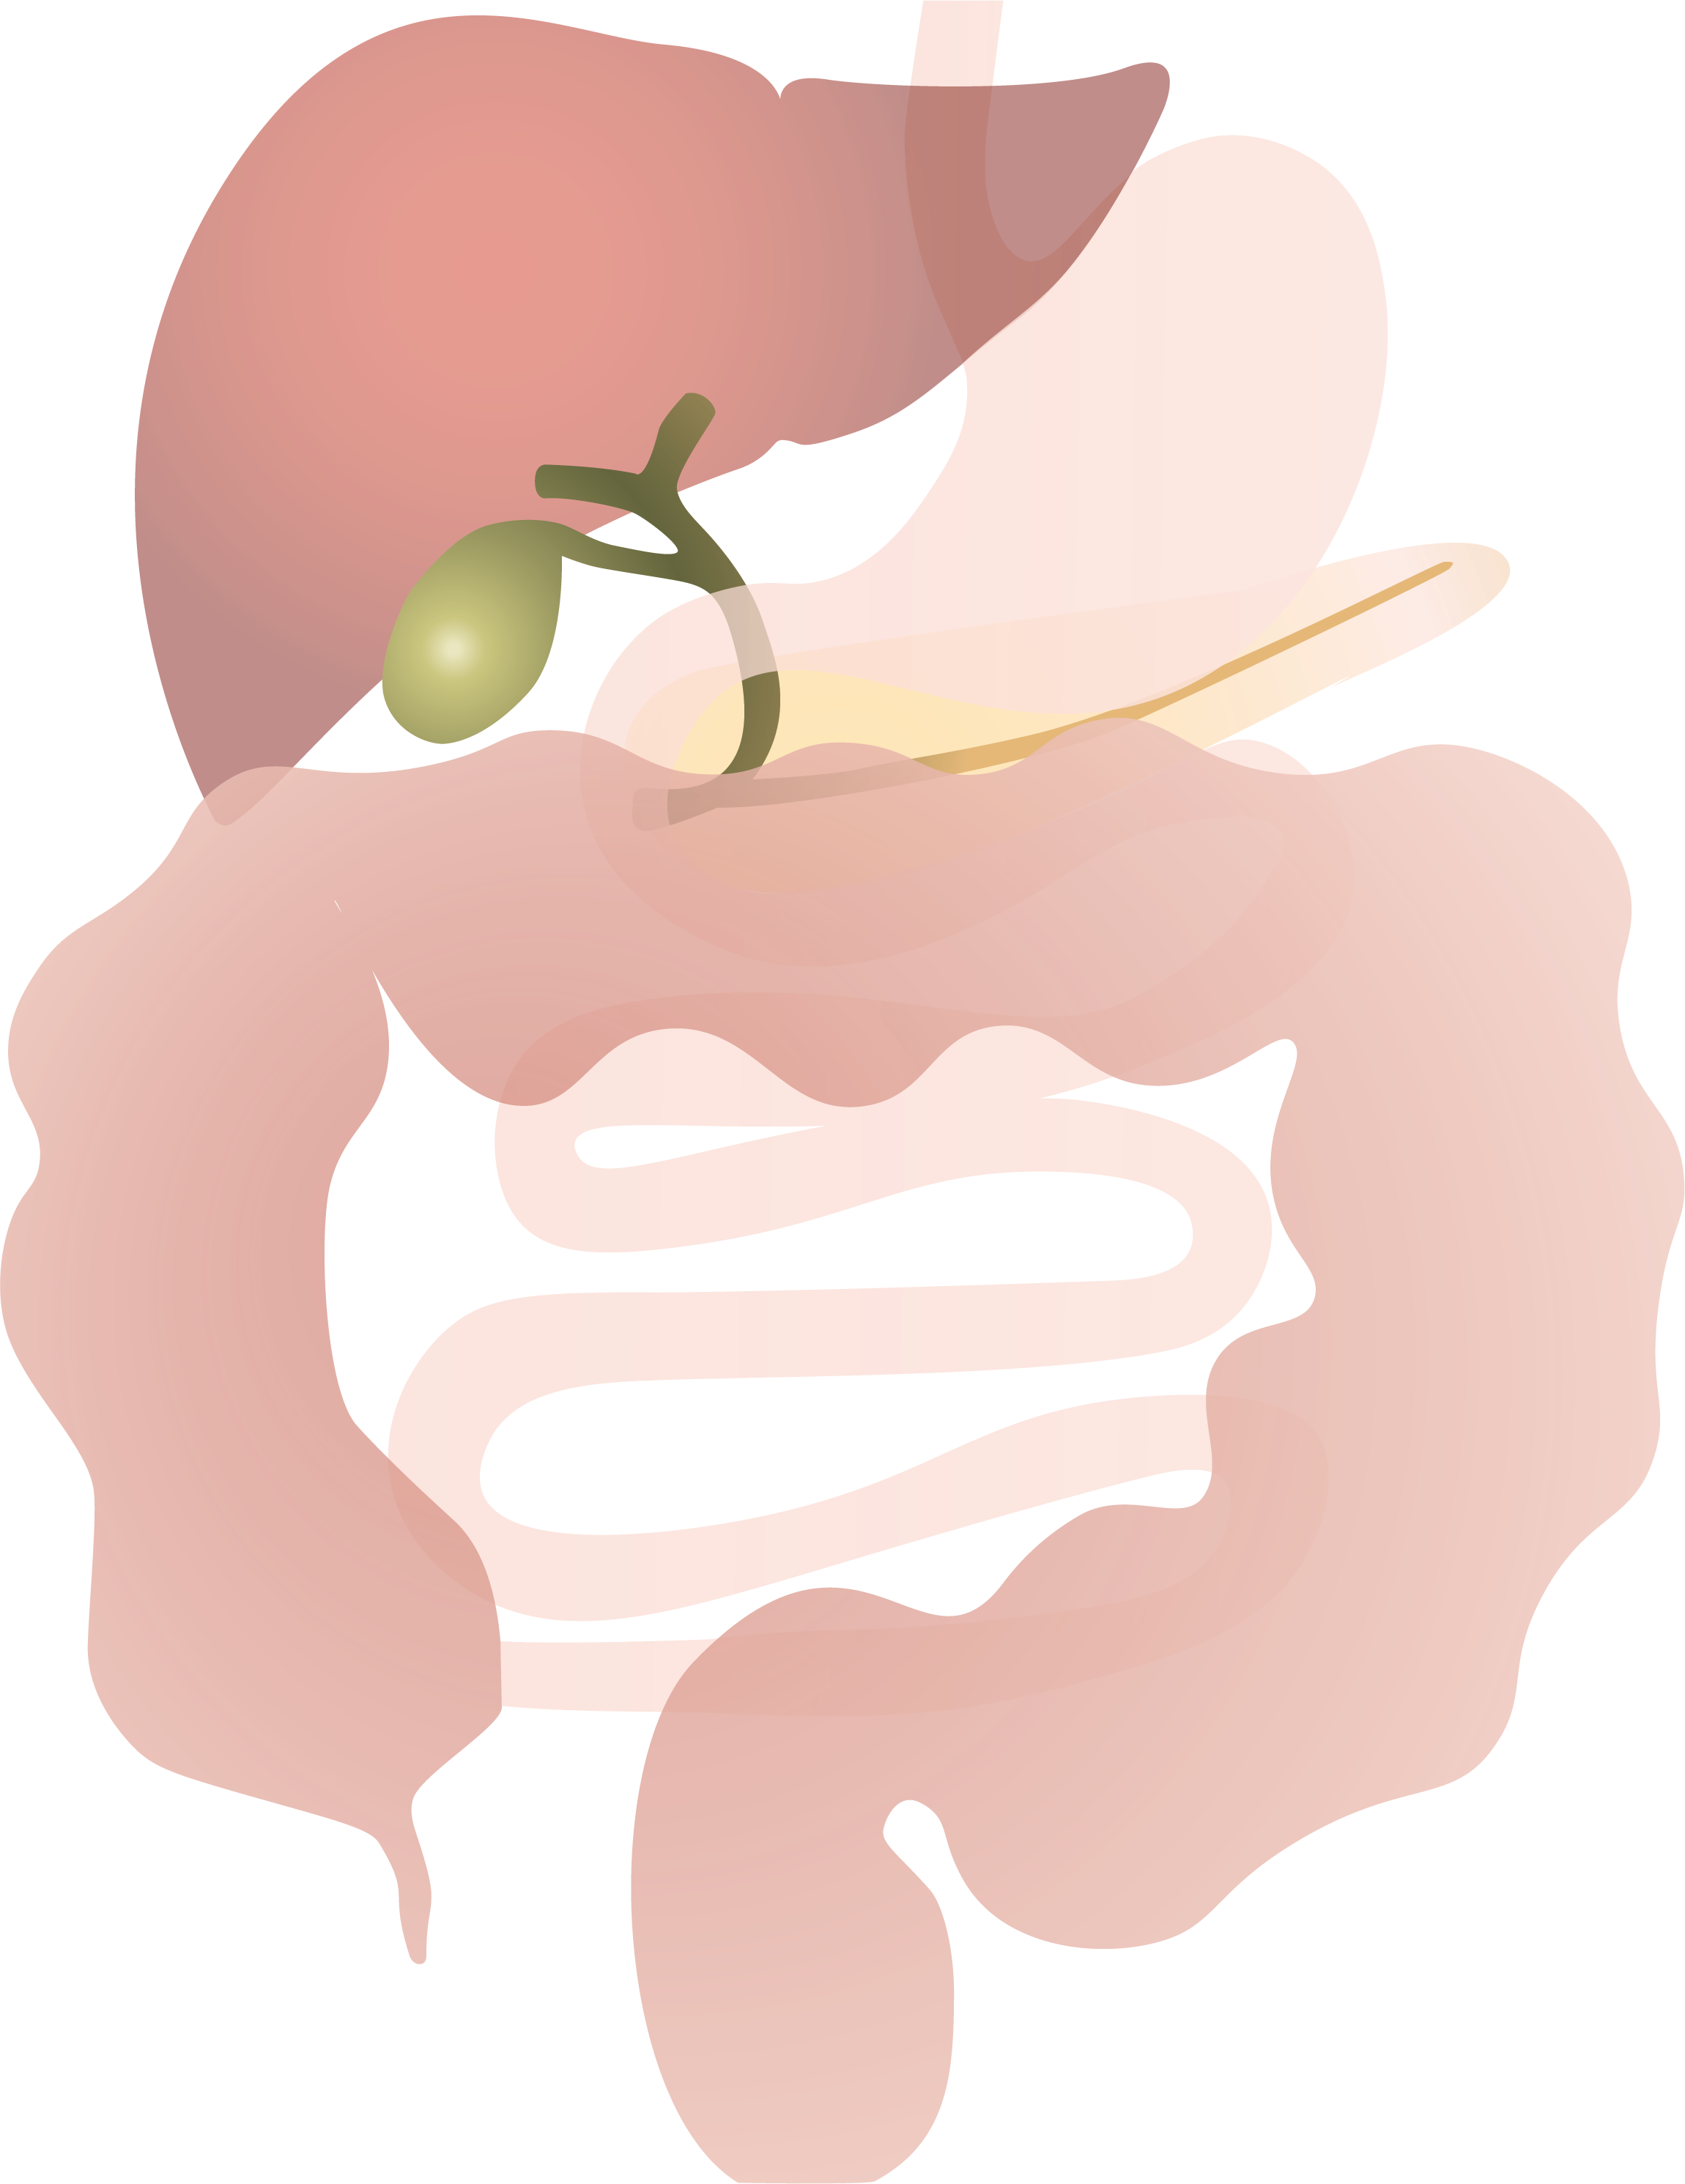

Dikkedarmkanker, ook wel colonkanker of coloncarcinoom genoemd, is een veelvoorkomende en potentieel levensbedreigende aandoening die ontstaat in de dikke darm, het laatste deel van het spijsverteringsstelsel. Deze vorm van kanker ontstaat doorgaans uit een ongecontroleerde groei van slijmvlies tot poliepen die, indien onbehandeld, verder kunnen uitgroeien tot kwaadaardige tumoren.

Bij een operatie voor darmkanker verwijdert de chirurg behalve de tumor aan beide kanten van de tumor ook een stukje gezond weefsel en een deel van het vet met lymfeklieren vlak bij de tumor. Deze lymfeklieren worden nadien onderzocht onder de microscoop. Afhankelijk van de uitslag bepaalt de arts of er een reden is om aanvullend chemotherapie te adviseren.

Afhankelijk van de locatie van de tumor moet dus een ander stukje van de dikke darm en zijn bloedvoorziening worden mee weggenomen.

Naargelang de plaats van de aandoening spreekt men van een: